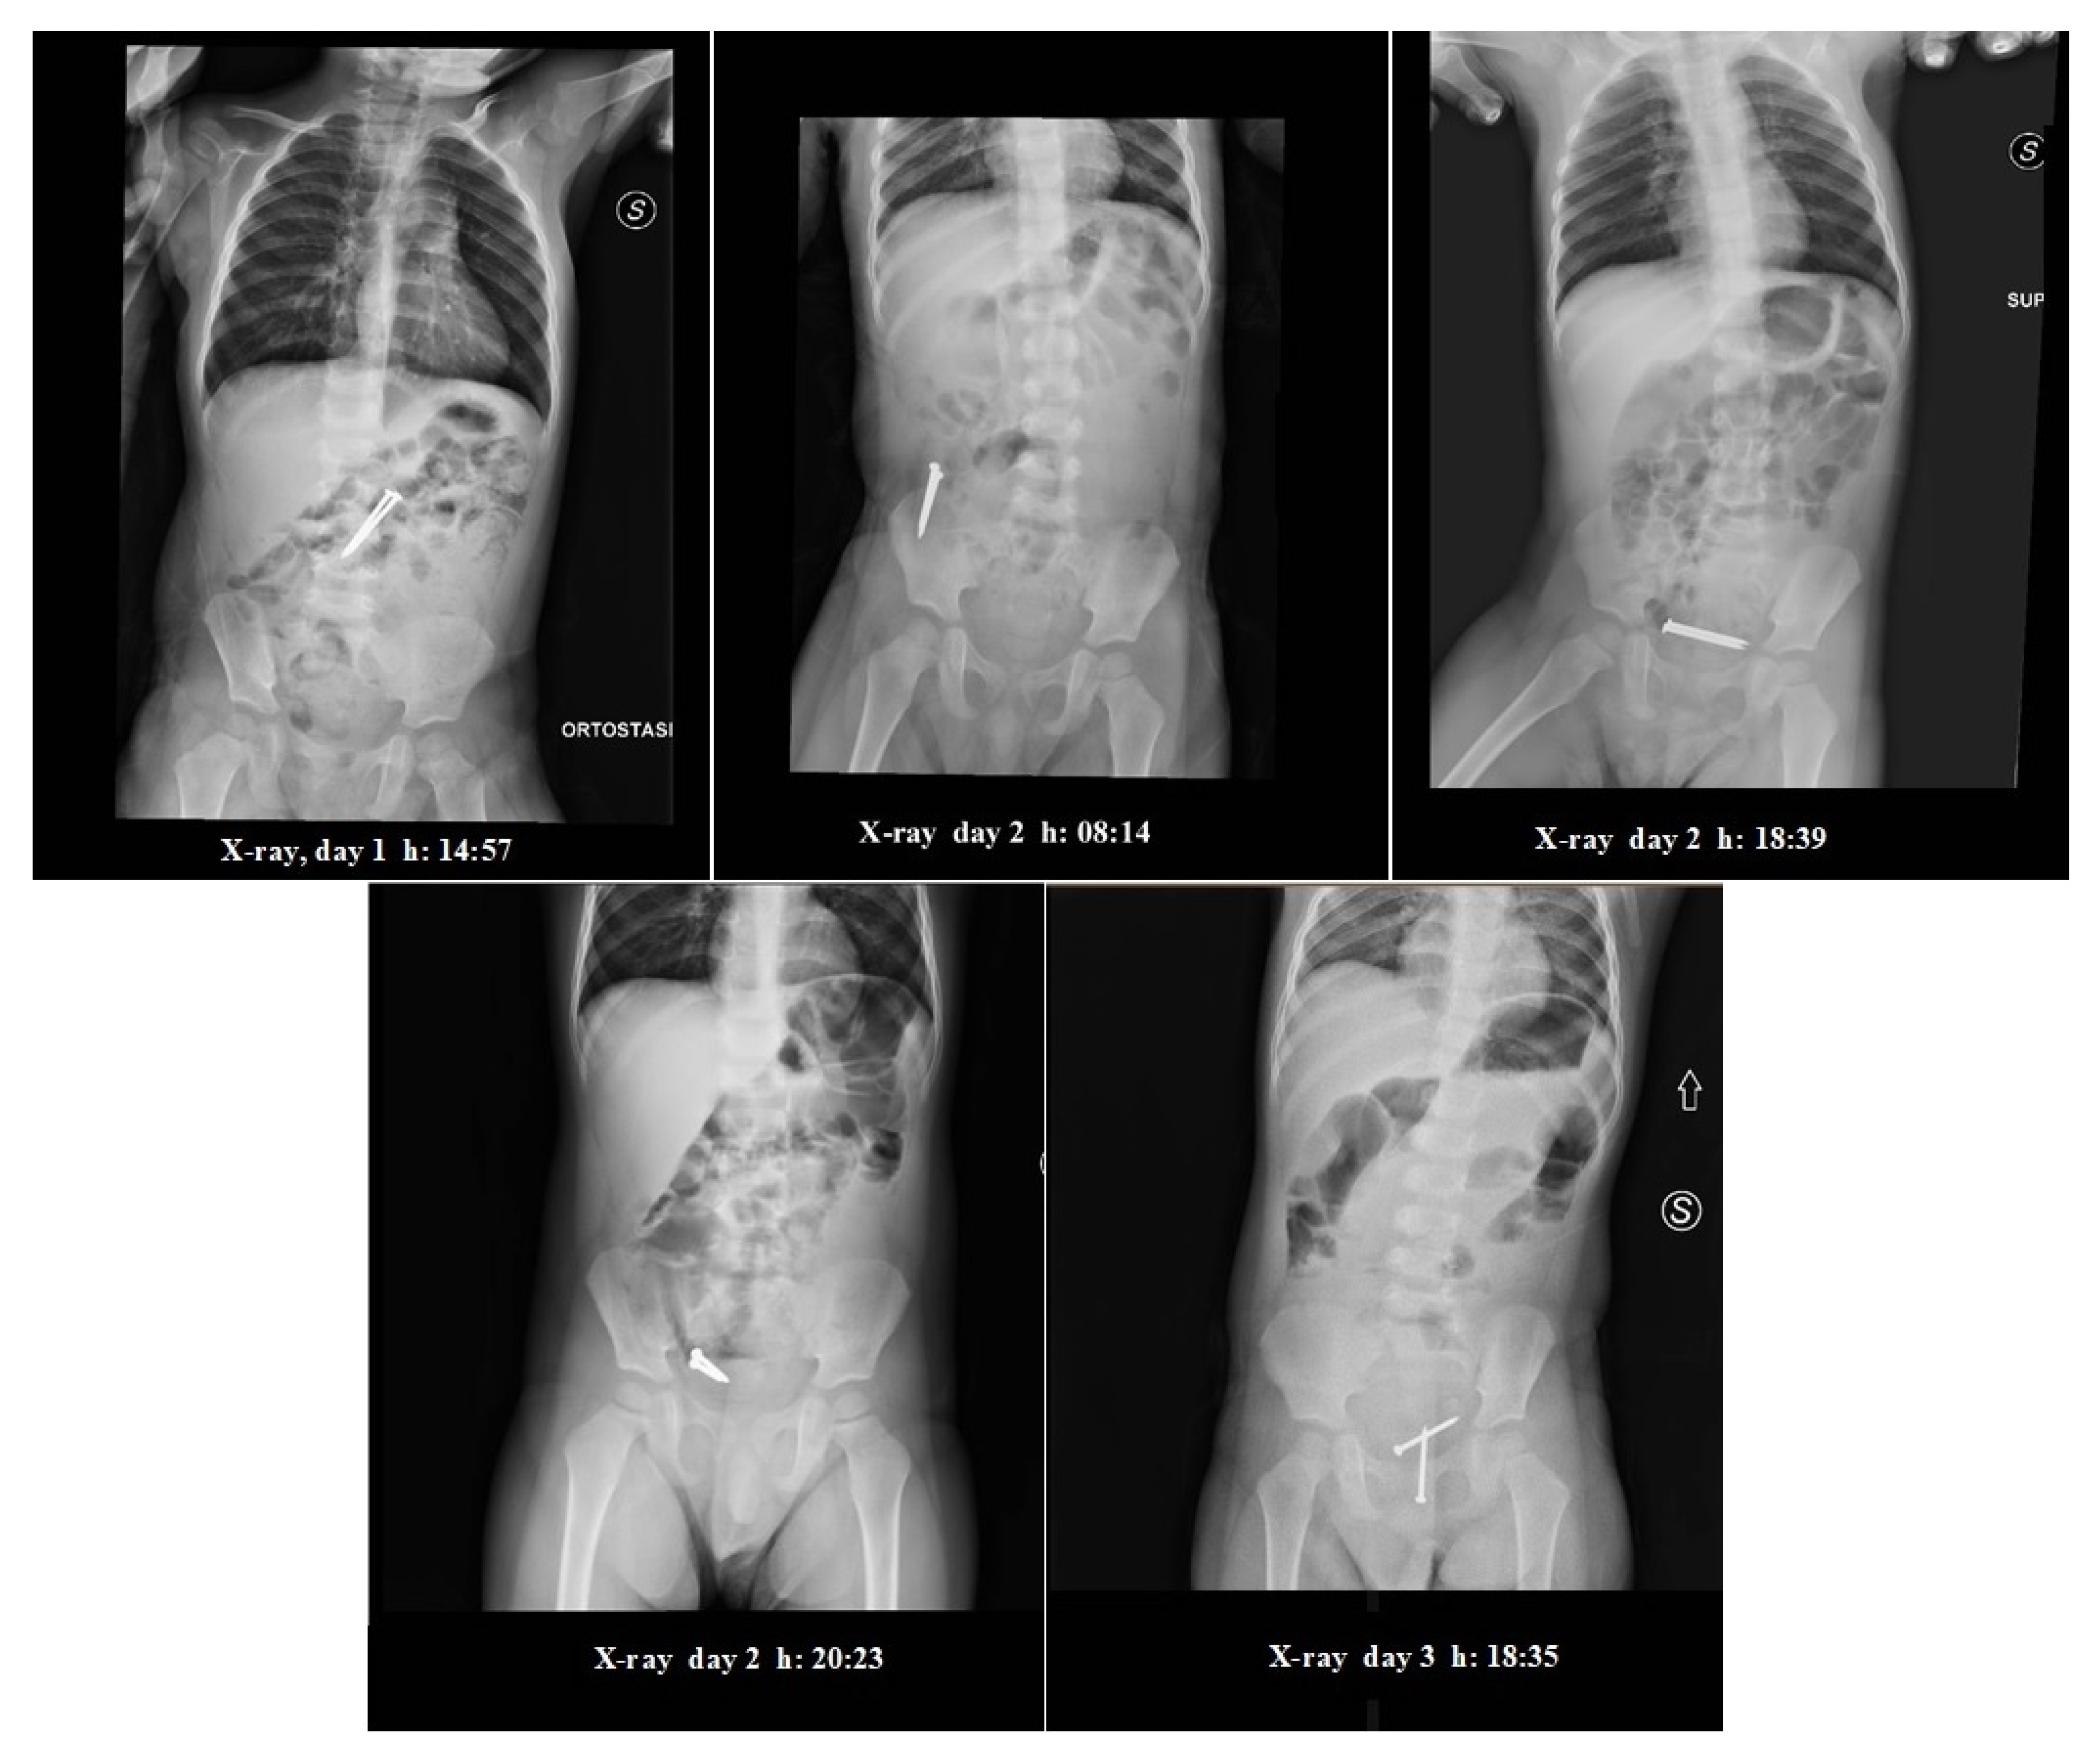

The first examination assessed that the child was awake, aware and in a stable condition, with no dysphagia or abdominal pain. His abdomen showed no signs of peritonitis. A new X-ray (Figure 1) of the abdomen confirmed the two “nails”—like radiopaque shadows over the ligament of Treitz, with no evidence of free gas under the domes of the diaphragm. Since neither clinical nor radiological signs of perforation were present, putting the FBs in the small bowel, a non-operative expectant management was followed.

During the hospitalization, the patient showed no signs of abdominal pain, discomfort or clinical relevance. A new X-ray in supine position (Figure 1) was taken the morning after (2nd day), around 8 am which showed progression of the FBs up to the right iliac region. The FBs kept close proximity to one another. The medical evaluation showed nothing out of ordinary. The patient had not evacuated. Upon consulting with the pediatric surgeon, an enema administration (20/Kg) was performed, after which the patient was allowed to consume liquids (water, tea) and rusks. The patient then evacuated twice, producing normal stools without the FBs in them.

During the late afternoon (2nd day hospitalization), the patient showed sudden signs of distress and discomfort, albeit without vomiting, upon which an X-ray in supine position (Figure 1) was promptly taken, showing the FBs in the pelvic cavity, with a central positioning and one near to another, suggesting their presence in the rectal ampulla. There were no visible signs of free air in the abdomen, and some signs of air fluid levels and dilated loops of bowel.

In the following afternoon (3rd day hospitalization), upon assessing that there were no signs of pain or complications, upon presenting a single episode of vomiting in the late afternoon, an X-ray was taken (Figure 1), showing the presence of the two FBs in the rectum, with no signs of air fluid levels nor free air in the abdomen.

Figure 1. Serial abdominal X-rays.